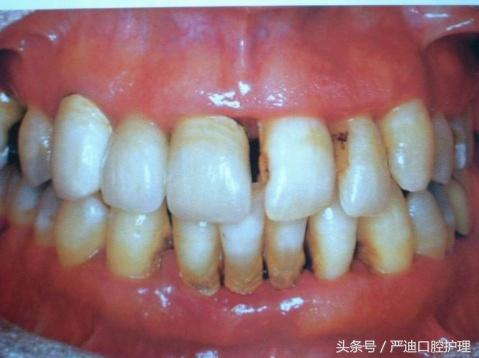

1.牙周炎

牙周炎會(huì)致使牙齦萎縮、牙槽骨吸收,也是形成黑三角的主要原因之一。

而平時(shí)若不注意口腔的清潔,沒有使用正確的刷牙方式,形成使用牙線、定期洗牙的習(xí)慣。牙結(jié)石就會(huì)變本加厲,堆積地越來越多,為菌斑提供養(yǎng)分。從而引發(fā)牙周組織的退縮。

牙周組織有軟組織和硬組織之分。

(1)軟組織:表現(xiàn)為牙齦萎縮,牙根表面暴露。

當(dāng)暴露的是比較窄長(zhǎng)的牙根時(shí), 較寬的牙間間隙易表現(xiàn)出“黑三角”現(xiàn)象。

(2)硬組織:牙槽骨吸收,牙槽嵴頂高度降低,導(dǎo)致鄰牙接觸點(diǎn)到牙槽嵴頂?shù)拇怪本嚯x增加進(jìn)而出現(xiàn)黑三角。